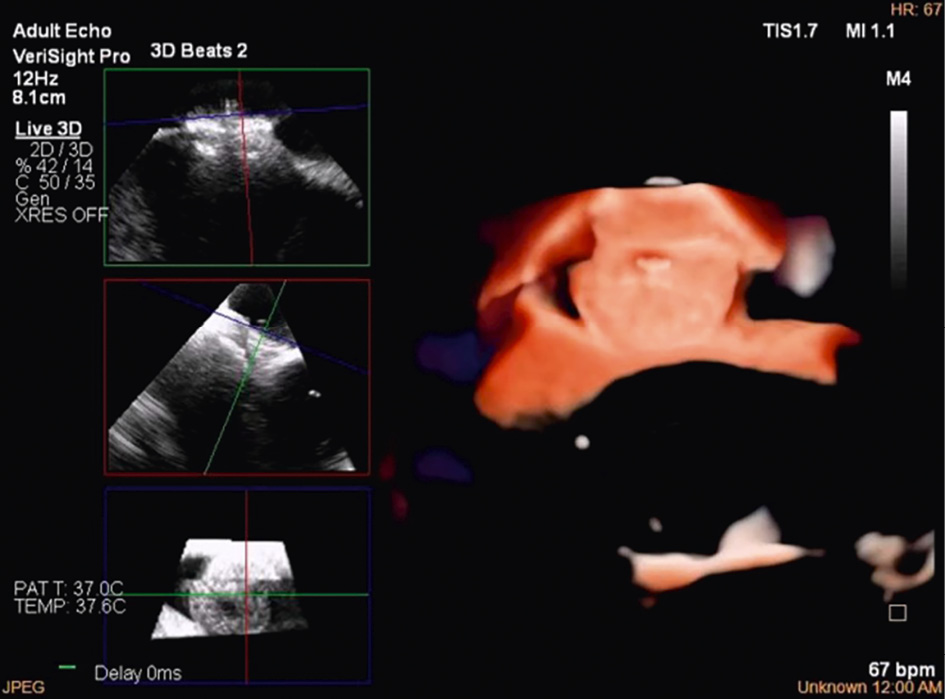

Imaging the MV with ICE implies crossing the interatrial septum and positioning the imaging catheter in the left atrium, a step that can be technically challenging. The TSP is performed using simultaneous biplane imaging with the ICE catheter positioned in the middle of the right atrium and retroflexed towards the septum (Figure 7A). A preshaped stiff wire is carefully positioned into the upper left pulmonary vein under fluoroscopic and ICE guidance (Figure 7B). Predilatation of the septum is required to facilitate the advancement of the ICE catheter into the LA while tracking the trajectory of the wire (Figure 7B). This can be done either by advancing and retracting the TEER-guiding catheter or through preparatory balloon septostomy using a 12-14 mm over-the-wire percutaneous transluminal angioplasty balloon. Once the ICE catheter has been placed successfully into the left atrium, it is followed by the guiding sheath, and the implant itself is then advanced towards the diseased MV (Figure 7C). While the ICE catheter usually follows the curve of the delivery system, a position below it (Figure 7D) or the use of the right and left deflexion knob minimises shadowing artefacts and avoids direct interaction with the TEER device or any other catheter used for the intervention. The key advantage of RT 3D catheters is the ability to produce MPR that facilitates simultaneous optimisation of the trajectory and orientation in several planes and on the 3D view from the atrium (Figure 8, Figure 9A-Figure 9B-Figure 9C, Moving image 9-Moving image 10-Moving image 11). At the end of the procedure, closure of the interatrial septum should be considered (Figure 9D), since the defect is usually larger than after conventional TEER due to the manipulation of two catheters through the same access. Closure can be easily guided with the ICE catheter back to the right atrium (Figure 9E). Mini-TOE or a paediatric probe (without 3D capabilities), as well as transthoracic echocardiography26 are additional confirmatory imaging modalities that can be used in combination with ICE (Figure 9F).

Figure 7. ICE-guided transseptal puncture. A) Transseptal puncture using biplanar imaging with the ICE catheter retroflexed in the middle of the RA. Needle tenting is seen simultaneously in two dimensions. B) Position of the delivery catheter over the diseased mitral valve. C) After wire placement and septum predilatation, the ICE catheter is moved into the LA following the trajectory of the stiff wire. A paediatric TOE probe without 3D capacity is inserted into the oesophagus. D) Position of the ICE catheter below the TEER system to avoid shadowing artefacts. 3D: three-dimensional; ICE: intracardiac echocardiography; LA: left atrium; RA: right atrium; TEER: transcatheter edge-to-edge repair

Figure 8. Three-dimensional true surgical view and left ventricular view of the mitral valve after TEER. A) 3D true surgical view; (B) left ventricular view. 3D: three-dimensional; TEER: transcatheter edge-to-edge repair

Figure 9. ICE-guided mitral valve transcatheter edge-to-edge repair. A) Implantation of two clips and leaflet capture under ICE visualisation; (B) final result after implantation of two clips for correction of a posterior flail; (C) 3D ICE view of the MV after implantation of two clips; (D) large iatrogenic ASD visualised from the right atrium and crossed by a wire; (E) ASD closure using a 14 mm Amplatzer Septal Occluder under ICE guidance; (F) final result with mild residual MR as shown by transthoracic echocardiography at discharge. 3D: three-dimensional; ASD: atrial septal defect; ICE: intracardiac echocardiography; LA: left atrium; LV: left ventricle; MR: mitral regurgitation; MV: mitral valve; RA: right atrium; RV: right ventricle